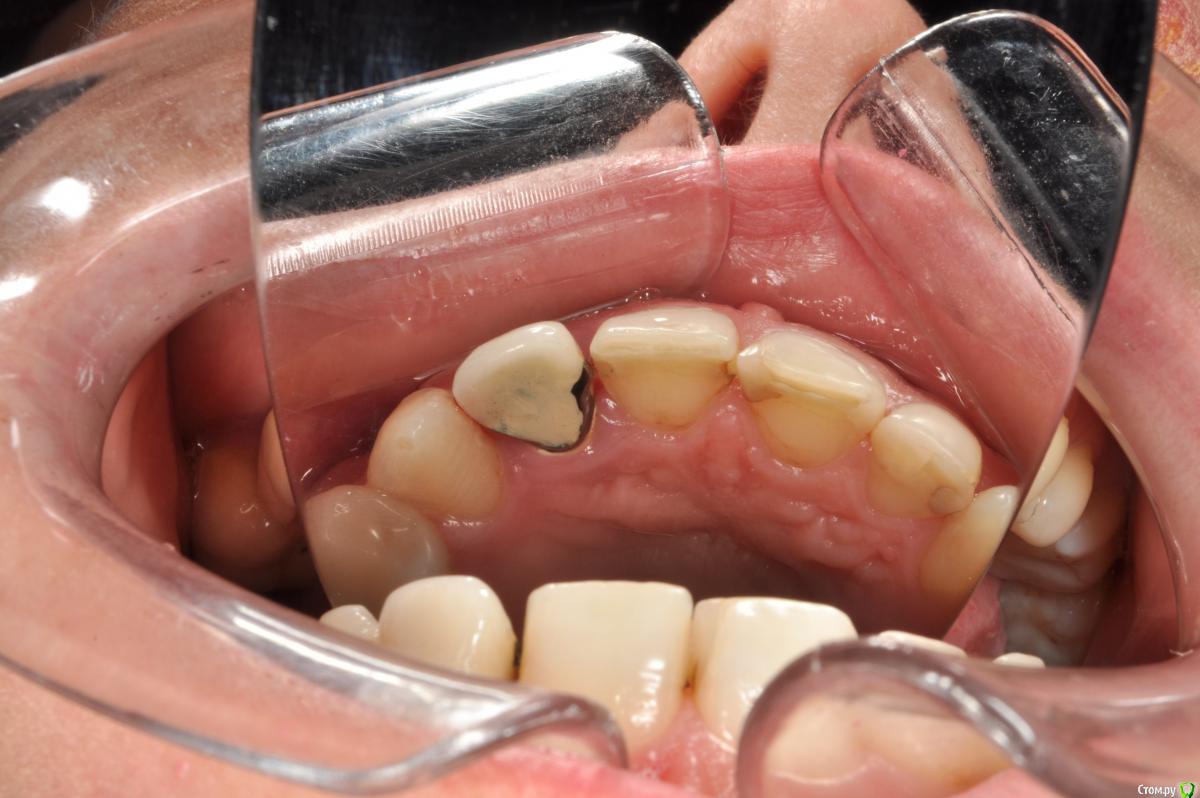

Пациентка 37 лет, не курит, соматически здорова. Частое выпадение ЛШКВ с коронкой. Диагностирована  фрактура вестибулярной стенки кореня зуба 22. Линия улыбки высокая. Биотип толстый.  Отсутствие вестибулярной пластинки, карман 8мм без ексудата.  Латеротрузия через 22.

Какая стратегия предпочтительней удаление корня 22, НКР, времянка понтик, потом имплантация с правельним наклоном. Или одномоментно с вестибулярным уклоном и в будущем  инд.абатмени+цементная фиксация.